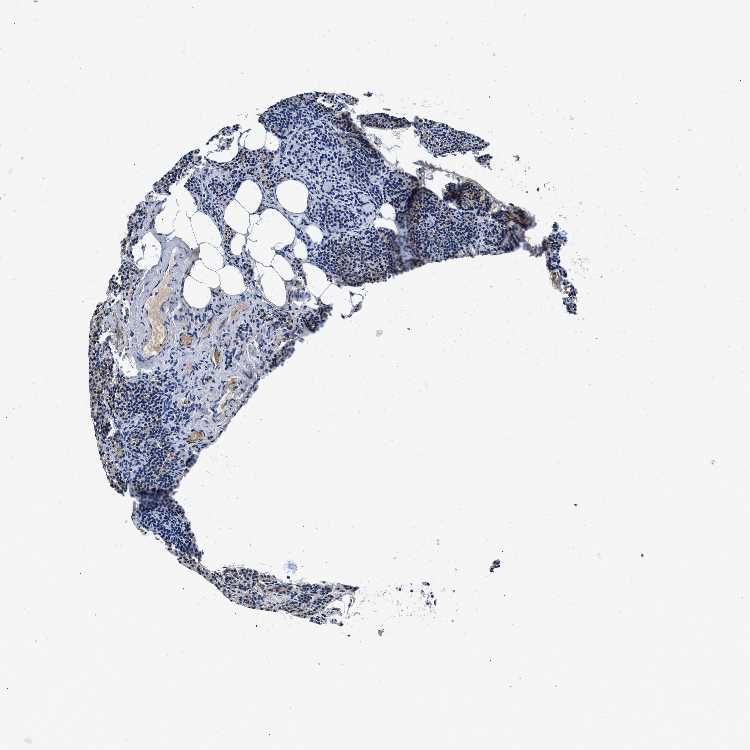

PARATHYROID GLAND - Antibody stainingi

Antibody staining in the annotated cell types in the current human tissue is reported as not detected, low, medium, or high, based on conventional immunohistochemistry profiling in selected tissues. This score is based on the combination of the staining intensity and fraction of stained cells.

Each image is clickable and will lead to virtual microscopy that enables deeper exploration of all samples and also displays staining intensity scores, fraction scores and subcellular localization as well as patient and tissue information for each sample.

Antibody HPA016755

Glandular cells Medium